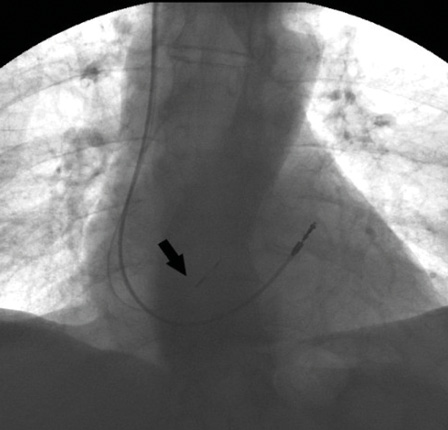

Рис. 2. Интраоперационное изображение с электрофизиологического монитора во время отключения электрокардиостимулятора. Отмечается нарушение внутрижелудочкового проведения по типу блокады правой ножки пучка Гиса и блокады передней ветви левой ножки пучка Гиса. Регистрируются эндограммы c аблационного катетера: фибрилляции предсердий (FP), проводящей системы (H) и высокоамплитудные желудочковые эндограммы (RV). На данном рисунке эндограммы H и FP трудно различимы между собой, однако стимуляция с картирующего электрода данной области позволяла получить стимуляционный комплекс, идентичный с нативным. Более выраженную эндограмму пучка Гиса зафиксировать не удалось. Предположительно, это связано с ранее проведенной аблацией атриовентрикулярного соединения

Рис. 3. Рентгенограмма после имплантации. Отражено два электрода: прежний, установленный в выходном тракте правого желудочка, и новый, имплантированный в область пучка Гиса (указан стрелкой)